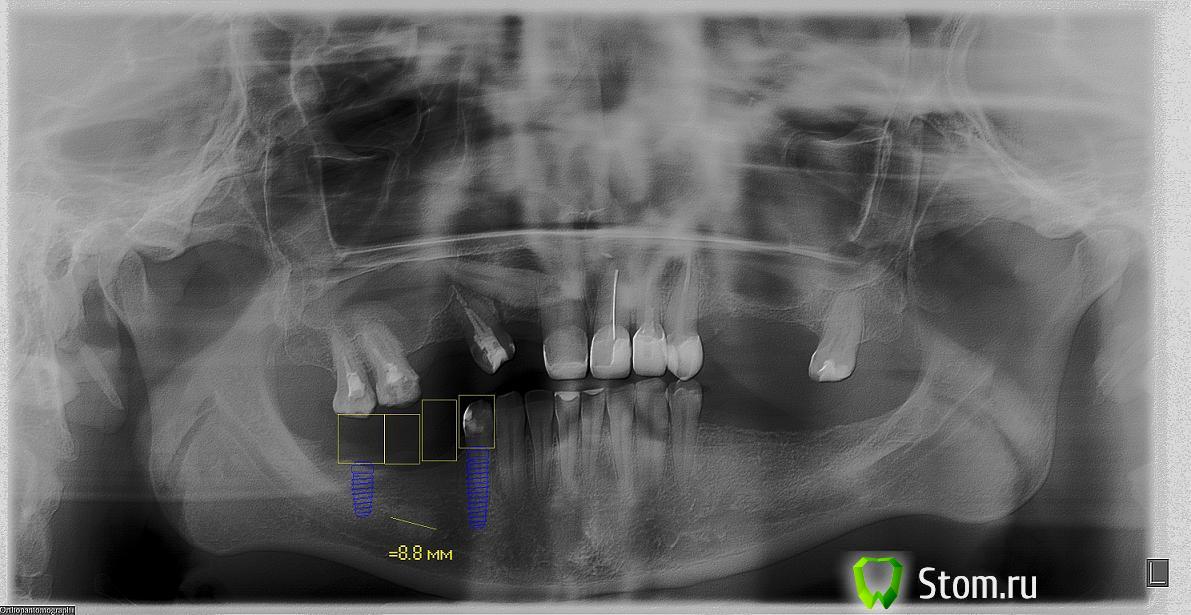

bullbull Опубликовано 16 января, 2012 Поделиться Опубликовано 16 января, 2012 (изменено) Пациентка Г. 35 лет. Обратилась в клинику для протезирования. В результате обследования обнаружено образование в области удаленного 46 зуба. Клинически данное образование никак себя не проявляет. Можно ли предложить подобный способ протезирования (на ОПГ), если пациентка откажется от радикального лечения в условиях стационара?P.S. На ОПГ полуторогодовалой давности размер образования не изменился. Изменено 16 января, 2012 пользователем bullbull Ссылка на комментарий

Elenushka Опубликовано 16 января, 2012 Поделиться Опубликовано 16 января, 2012 как по мне похоже на остеому,всю жизнь может не проявляться.там 2импл планируете? Ссылка на комментарий

Bier Опубликовано 16 января, 2012 Поделиться Опубликовано 16 января, 2012 я бы еще имплантат 45 поставил, можно короткий. Но вообще остеому бояться не надо. Ссылка на комментарий

ПалСаныч Опубликовано 16 января, 2012 Поделиться Опубликовано 16 января, 2012 С позволения коллег выложу свое мнение:1. эта остеома не нуждается в радикальном лечении при отсутствии симптоматики2. противопоказаний для импланта нет3. 2 имплантата мне кажется маловато для такого промежутка4. Гребень в области остеомы узковат. Я бы сначала поставил блок Имхо Ссылка на комментарий

bullbull Опубликовано 16 января, 2012 Автор Поделиться Опубликовано 16 января, 2012 Планируем 3 или 4 импланта. Сомнения в том, что не "разбудим" ли мы эту штуковину?Наиболее вероятно - остеома, но нет четких контуров. А это более характерно для участков внутрикостного склероза.Может стоит перед лечением взять биопсию? Ссылка на комментарий

Elif Опубликовано 17 января, 2012 Поделиться Опубликовано 17 января, 2012 я тоже думаю это остеома, мое мнение если образование в течение полутора года ни как не изменился и жалоб никаких нет лучше не трогать, а имплантат ставить как планировали на ОПГ 44 и 47 и мостовидный протез Ссылка на комментарий